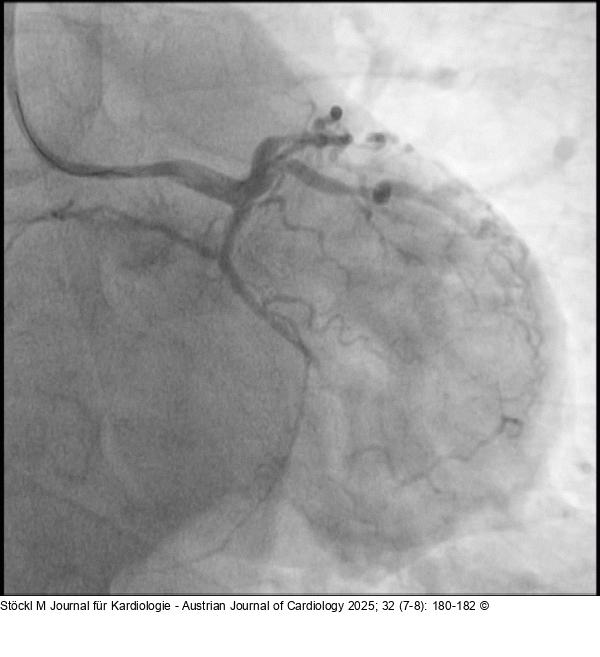

Abbildung 3: CX CX: chronischer Verschluss eines Marginalastes |